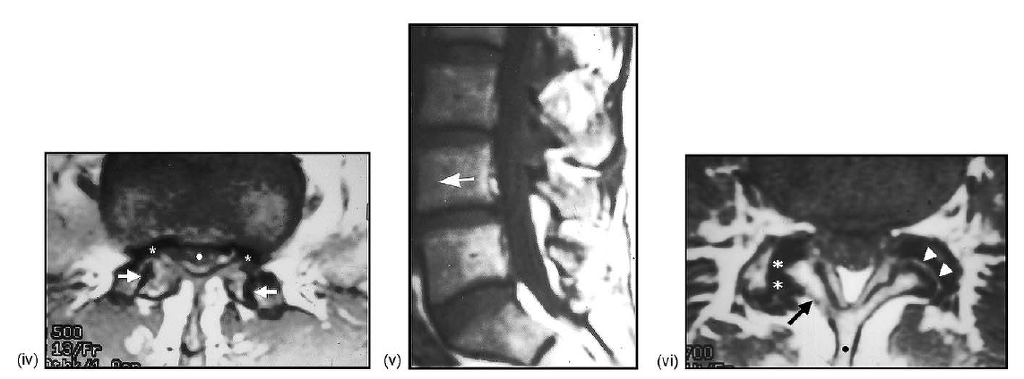

(iv) Coronal T2-weighted, fat-suppressed MRI showing again the apparent cystic degeneration of the interspinous ligament situated between the spinous processes of L4 and L5 (dots; compare with iv). (v) Axial T1-weighted MRI showing multiple rounded paraspinous soft tissue structures (arrows); also note the spinous process of L5 (black dot) and the redundant-hypertrophic inter-supraspinous ligament(s) (white dot) (compare with (D)). (vi) Axial T2-weighted, fat-suppressed MRI showing the hyperintense nature of the paraspinous cysts (arrows; same patient in (E) v–vi).

(i) midline sagittal T1-weighted MRI showing hyperintensity of the interspinous ligaments at multiple levels (asterisks). (ii) Midline sagittal T2-weighted, fat-suppressed MRI showing isolated hyperintensity of the L5-S1 interspinous space (arrow) indicating degeneration and possible cystic alteration of the interspinous ligament (compare with (A)). (iii) Coronal T1-weighted MRI showing the rounded appearance of the interspinous ligament (arrow), between the spinous processes of L5-S1 (dots).